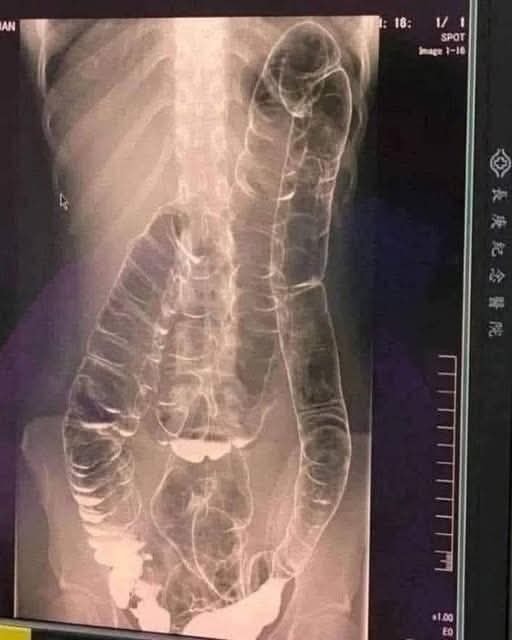

When waste accumulates in the colon due to an inefficient digestive system, it causes severe discomfort and bloating. Over time, the colon expands beyond its normal size, struggling to contain the excessive buildup of feces. In this case, medical imaging revealed a severely distended colon that had enlarged so much it reached up toward the chest, dangerously close to the heart. The stretching had nearly erased the colon’s natural folds and wrinkles, essential for its proper function. Left untreated, this condition could have led to life-threatening complications.